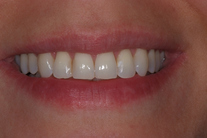

Tandreglering 5

32-årig kvinna som tycker att hon bara visar sina framtänder. En utjämning och vidgning av tandbågen med 8 månaders genomskinliga Invisalignskenor, gav henne ett fint leende.